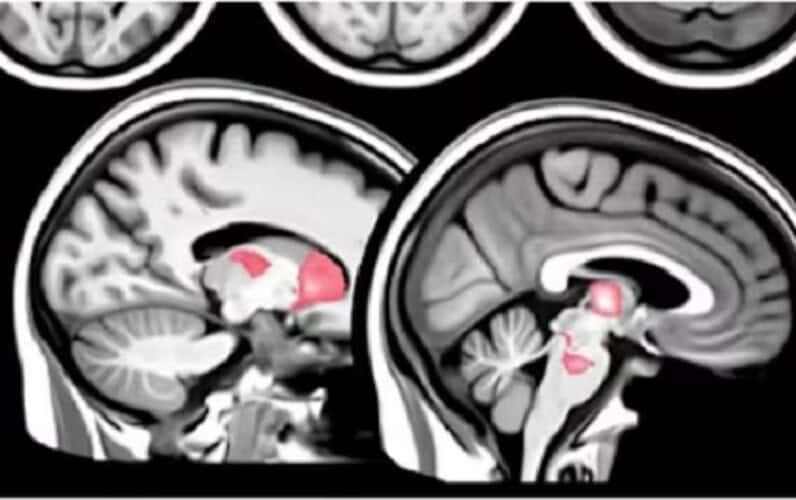

Nova studija otkriva da mRNA „vakcine“ izazivaju abnormalne imunološke reakcije, koje dovode do dugoročnog oštećenja mozga.

Naučnici su postavili hipotezu da su postojani neurološki simptomi nakon mRNA vakcinacije povezani sa abnormalnim imunološkim odgovorima.

Ovi odgovori uključuju generaciju autoantitela i poremećaj urođenog imunološkog sistema.

Naučnici su ustanovili da kohorta „vakcinisanih“ pati od postojanih neuroloških simptoma i suočava se sa rizikom od dugoročnih oštećenja.

Biopsije kože potvrdile su smanjenje gustine malih nervnih vlakana, podržavajući povezanost sa malim vlaknima neuropatije (SFN).

Ova zapažanja sugerišu da PASC-vac može biti pokrenut neadaptivnim humoralnim i urođenim imunološkim odgovorima nakon mRNA vakcinacije protiv Kovida.